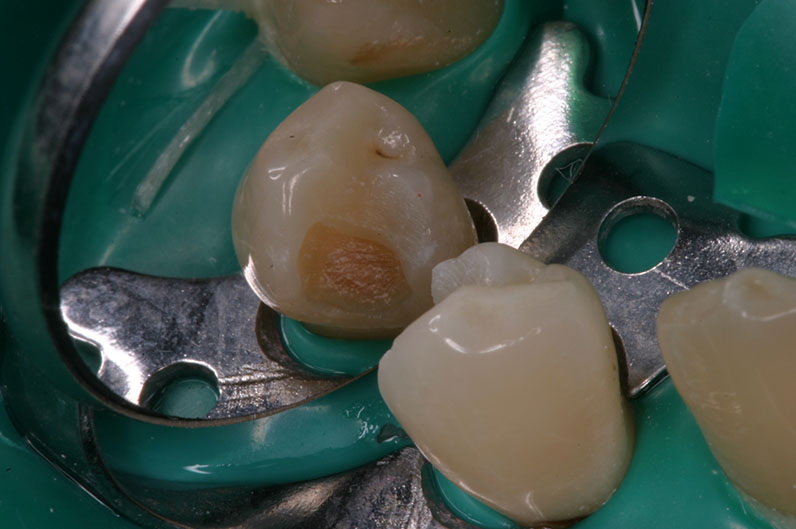

перед экскавацией кариеса